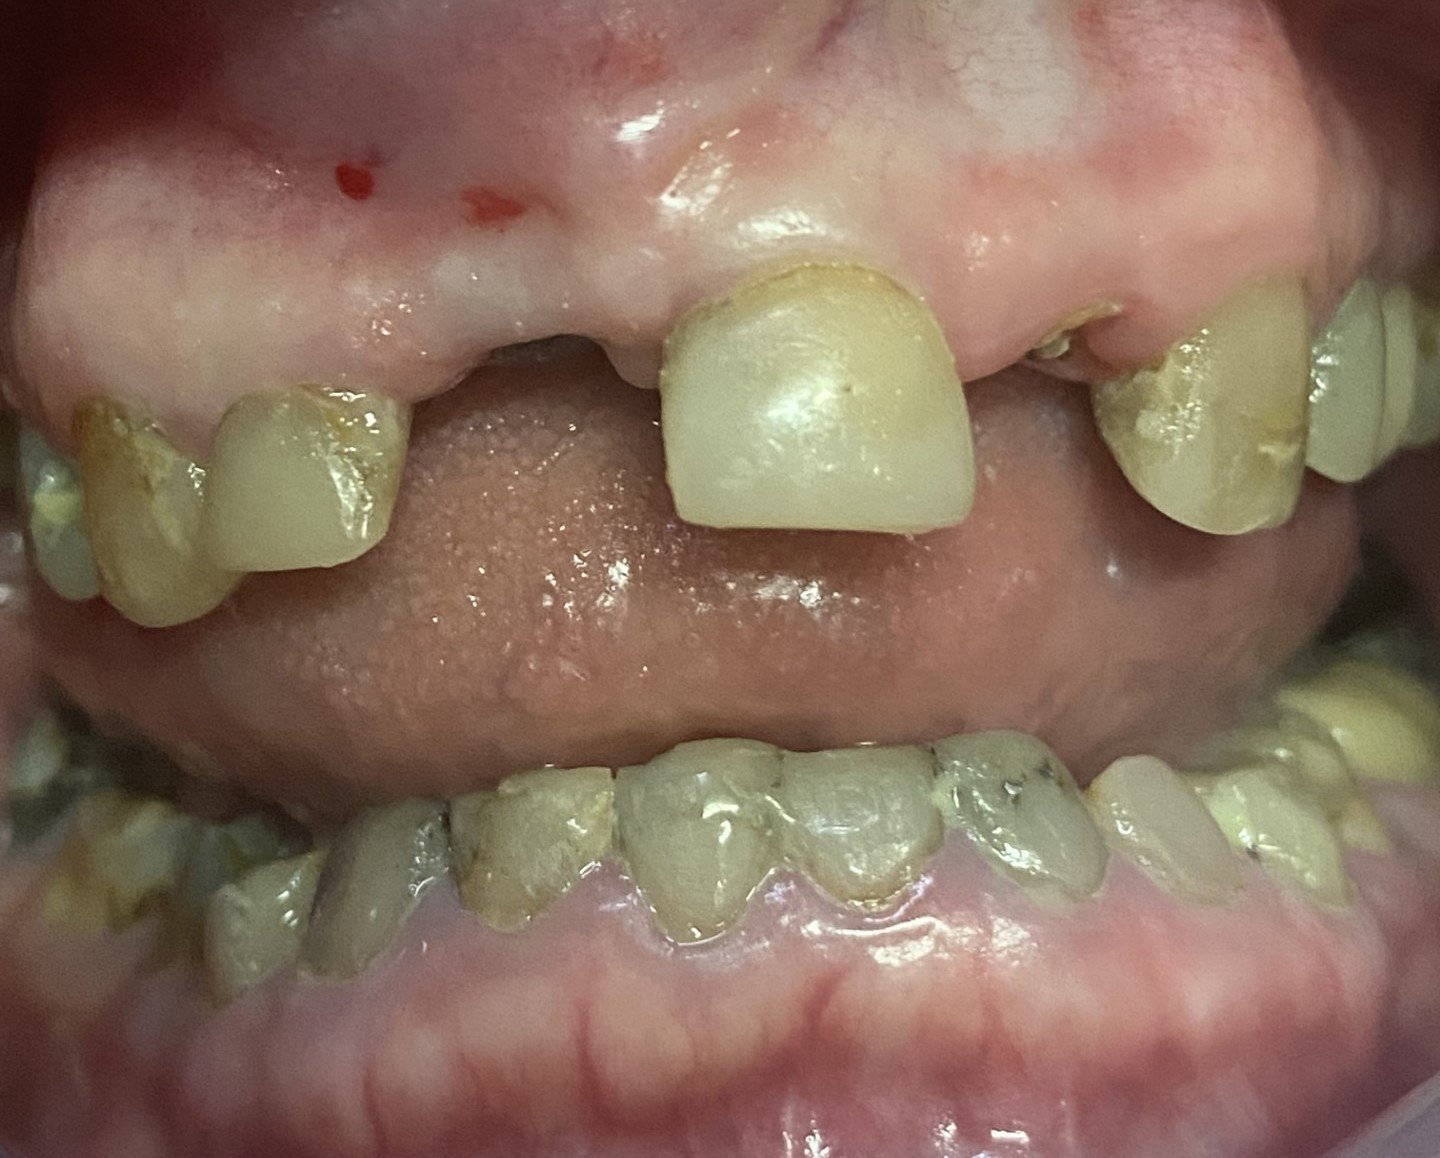

This 65 year old patient had numerous dental problems including decay, periodontal gum disease involving moderate to concerning future bone loss, missing teeth, heavily filled teeth and an extremely difficult very deep overbite.

-

Part of the deep overbite and a heavily discoloured top left number 2 lateral incisor previously extracted, root sectioned and amalgam filled prior to reattaching as a bonded bridge tooth to the adjacent top left number 3 canine tooth.

The remaining lower 6 front teeth that were deemed to have insufficient bone for longevity and unsuitable for a bite reconstruction, these teeth were extracted.